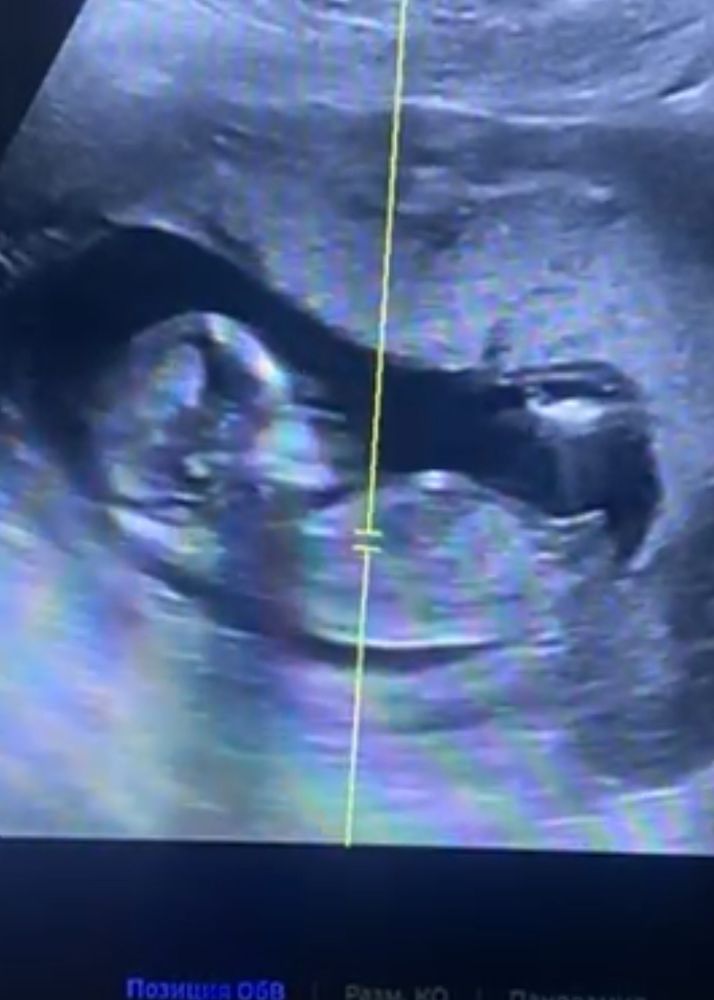

Пол ребенка по половому бугорку

Беременность Пол малыша на 13 неделе

Катя Воробьева, чуть осталось🥹 мне кажется парень 🙂кверху как то там все😂

А мне кажется мальчик , более вздернут что ли

На девочку похоже)

Мне кажется девочка